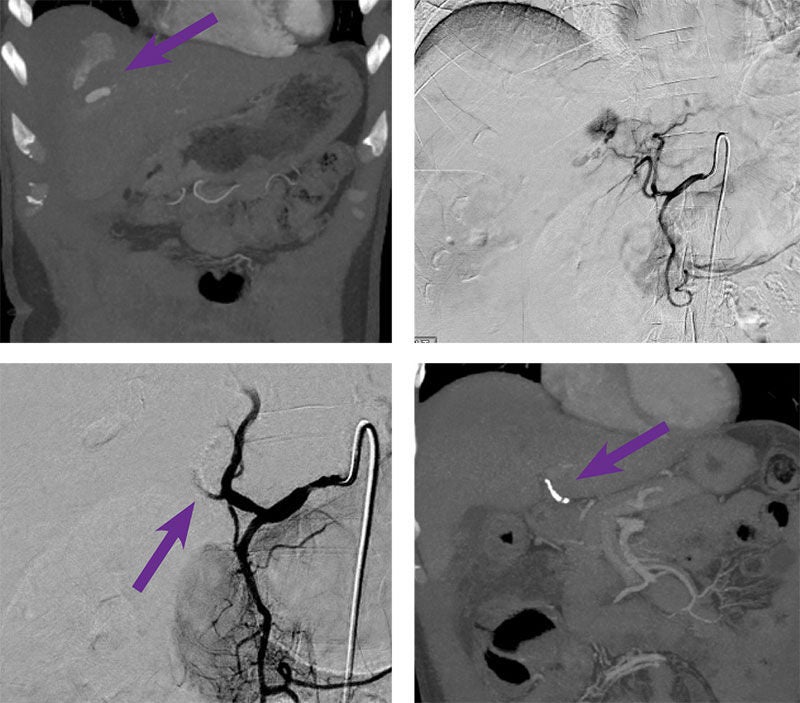

Hepatic artery embolization

Courtesy of Dr. Osmanuddin Ahmed I University of Chicago

40-year-old male presented with right upper quadrant stab wound.

Intervention used

Arterial access was gained via the right common femoral artery. A Simmons 1 catheter was used to select the celiac artery and angiography was performed. Through the 5 F catheter, a 2.8 F Progreat™ Microcatheter and Fathom™ Steerable Guidewire was advanced into the left hepatic artery and angiography was performed. The segment 4 hepatic artery was catheterized and arteriography demonstrated a blush protruding from off the branch. 0.2 cc of Obsidio Embolic (purple arrow) was injected via the segment 4 artery. Follow-up angiography demonstrated successful occlusion of the segment 4 artery and resolution of the blush.

Outcome

Patient stabilized immediately following embolization. The patient was discharged after 5 days.

Purple arrows pointing to hepatic artery embolization with Obsidio.